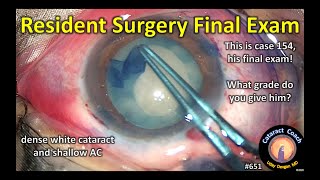

Resident Cataract Surgery (case #32) resident cataract surgery final exam!

resident cataract surgery final exam! CataractCoach 1633: I am amazed by this resident cataract surgery

Resident Cataract Surgery (case #32) resident cataract surgery final exam!

resident cataract surgery final exam! CataractCoach 1633: I am amazed by this resident cataract surgery